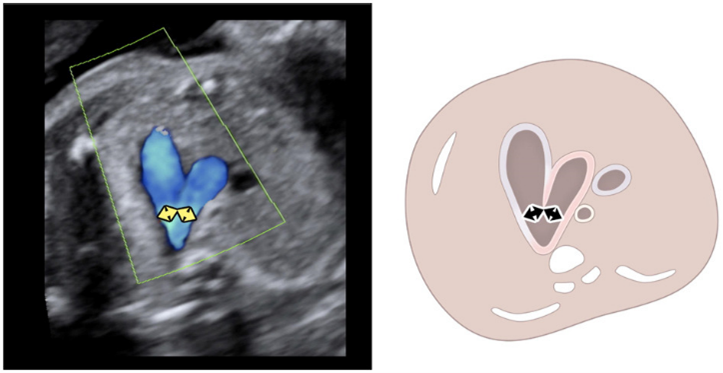

AI screening assistant for fetal heart and brain

Fetoly is the first real-time AI solution for fetal ultrasound, helping to ensure a complete and standardized examination. Integrating with most ultrasound systems, it provides instant feedback to help diagnostic confidence and help improve pregnancy outcomes.

• Real-time ratios supporting the detection of pathologies